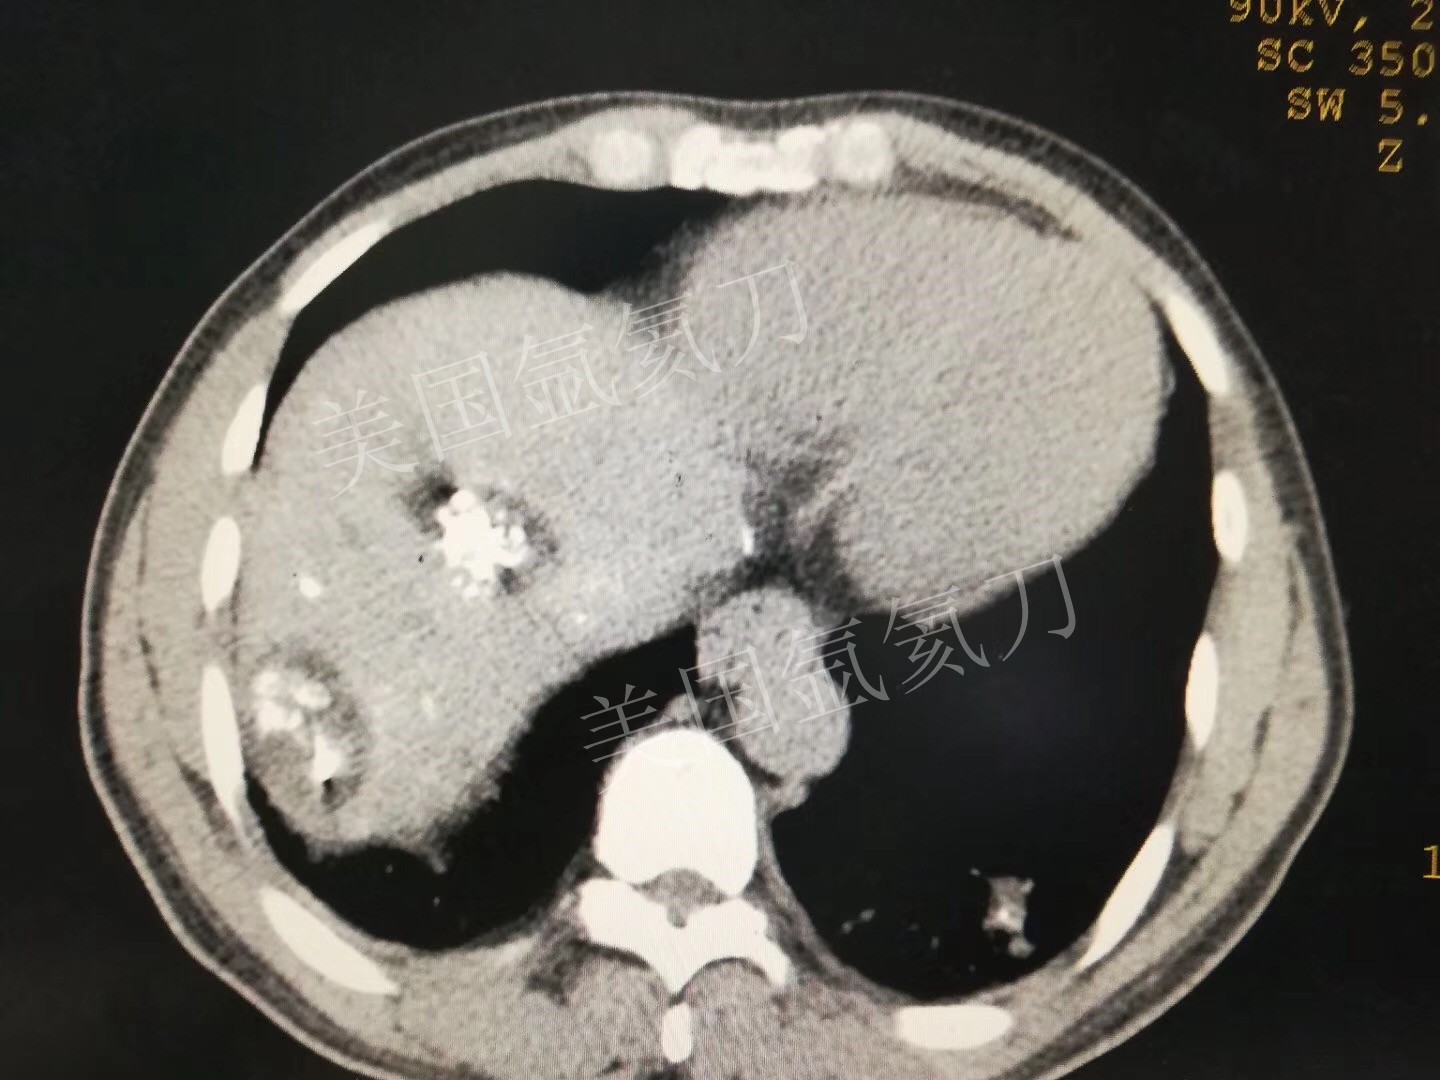

氩氦刀消融两个3公分介入后病灶,疗效确切!